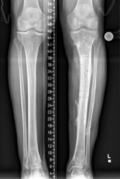

Von der Fraktur über die Pseudarthrose zum Segmenttransport

Vorgeschichte: Herr M. zog sich vor drei Jahren im Rahmen eines BG-lich versicherten Motorradunfalls eine I°ig offene mehrfragmentäre Tibiaquerfraktur mit 2-Etagen-Fraktur der Fibula links sowie eine OSG-Luxationsfraktur rechts zu.

Die initiale Versorgung erfolgte in einer Klinik der Maximalversorgung mit Fixateur extern Anlage und Transfixation des Sprunggelenks. Im Verlauf erfolgte der Verfahrenswechsel auf einen Tibia-Nagel links und Fibulaplatte mit Zuggurtung des Innenknöchels rechts.

Patientenbezogenen Angaben: Der Patient ist Mitte 40, gesund ohne relevante Vorerkrankungen, mit gutem AZ und leicht adipösem EZ. Der Patient ist Nichtraucher.

Beginn der Infektion: Etwa einen Monat später kam es beidseits zu Nekrosen und Wundheilungsstörungen, welche mittels Wundunterdruck-Therapie und im Verlauf Defektdeckung mittels Suralislappenplastik behandelt wurden.

Bei Fistel über der Unterschenkelfraktur links erfolgte etwa 9 Monate nach dem Unfall die Fistelexzision, mehrfaches Markraummüberbohren mit Jet-Lavage sowie die erneute Wundunterdruck-Therapie. Bei Keimnegativität erfolgte eine erneute Marknagelosteosynthese mit Schwenklappenplastik und Spalthaut zum Verschluss des Defekts.

Vorstellung in einem Zentrum: Ein Jahr nach dem Unfall erfolgte bei persistierenden Schmerzen die erstmalige Vorstellung in einer BG-Klinik. Hier zeigte sich eine Subluxationsstellung der Sprunggelenksfraktur auf der rechten Seite mit weit fortgeschrittener posttraumatischer Arthrose. Auf der linken Seite zeigte sich eine befriedigende Stellung bei noch erheblicher Defektzone lateralseits und nicht ganz aufeinander stehenden Frakturenden aber in regelrechter Position. Es erfolgte zunächst die Sprunggelenksarthrodese rechts um eine stabile, schmerzfreie Seite zu erhalten.

Rekonstruktion: Bei Infektverlauf mit Nachweis von Staphylococcus aureus und Staphylococcus epidermidis sowie histologischem Nachweis einer chronischen Osteomyelitis an der linken Tibia erfolgte 1,5 Jahre nach dem Unfall die Infektsanierung mit Segmentresektion und anschließend der Segmenttransport mittels Precice-Bone-Transport-Nail.

Nach etwa 2 Monaten konnte das Kompressionsdocking erfolgen. Bei weitgehender Konsolidierung über ein Jahr nach der Implantation erfolgte die Metallentfernung des einliegenden Segmenttransport-Nagels sowie die Anpassung eines Braces zur weiteren Ausbehandlung.

Resümee: Erst durch die konsequente Segementresektion konnte der Infekt eradiziert werden. Durch die Therapie mit dem noch relativ neuen Verfahren des Segmenttransportnagels konnte dem Patienten die zwar ebenfalls meist erfolgreiche, jedoch deutlich belastendere Therapie mit einem Ringfixateur erspart werden.